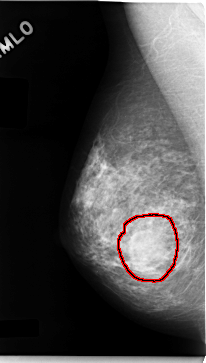

C_0060_1.LEFT_MLO

FILE: C_0060_1.LEFT_MLO.OVERLAY

TOTAL_ABNORMALITIES 1

ABNORMALITY 1

LESION_TYPE CALCIFICATION TYPE AMORPHOUS DISTRIBUTION CLUSTERED

ASSESSMENT 4

SUBTLETY 2

PATHOLOGY MALIGNANT

TOTAL_OUTLINES 1

BOUNDARY